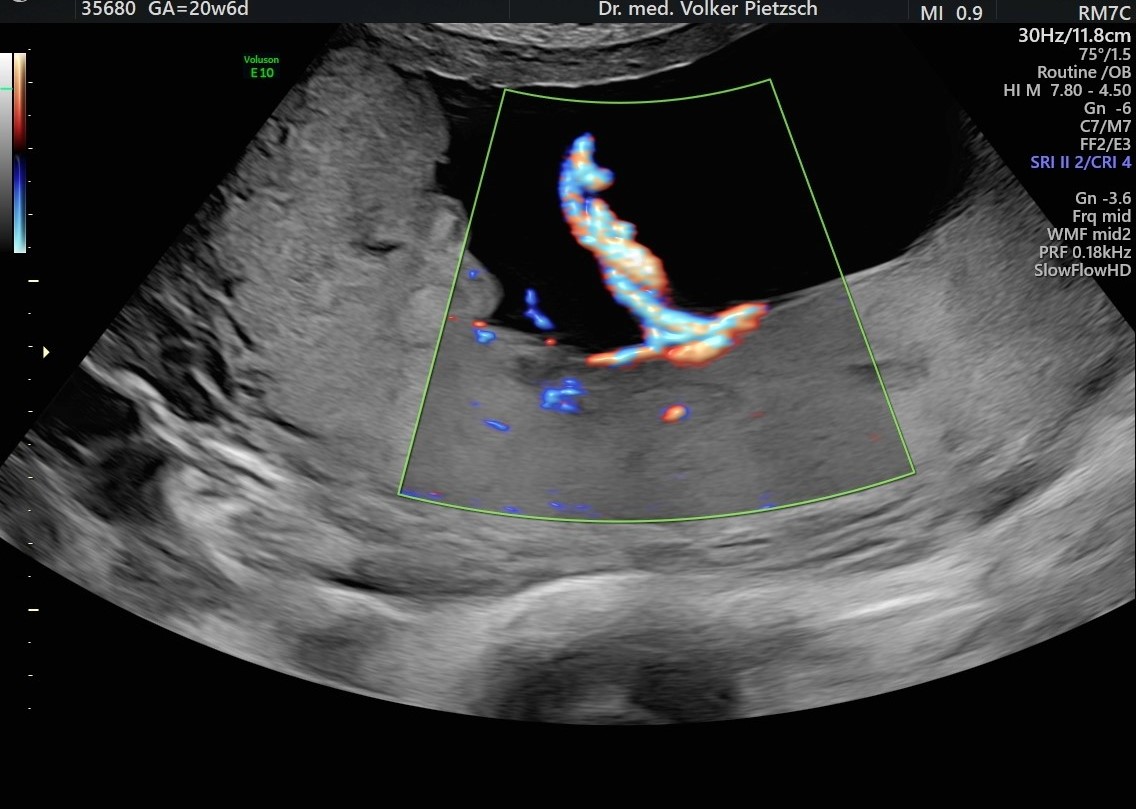

Feindiagnostik in der 20. – 22. Schwangerschaftswoche

Die Feindiagnostik im 2.Schwangerschaftsdrittel beinhaltet eine komplette Beurteilung des Kindes von Kopf bis Fuß, sie ist eine umfangreiche und differenzierte Diagnostik, bei der das fetale Organsystem im Mittelpunkt des Interesses steht.

Die Zielsetzung der Feindiagnostik in der 20. SSW ist es, Fehlbildungen, Erkrankungen des Foeten oder Versorgungsstörungen auszuschließen, um die Betreuung von Mutter und Kind in der Schwangerschaft oder nach der Entbindung optimieren zu können.

Der Fokus liegt primär auf dem Organsystem des Foeten, in diesem Bereich finden sich die häufigsten Probleme, die nachgeburtlich betreut werden müssen. Diese Untersuchung ist auch eine sinnvolle Ergänzung zur frühen Feindiagnostik der 12./13. SSW, die Beurteilung genetischer Risiken stehen in der 20.SSW nicht im Mittelpunkt.

: Die Plazenta mit der Nabelschnur und der Fruchtwassermenge